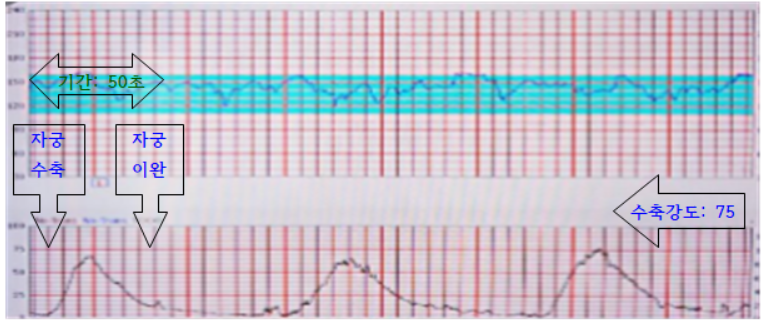

- [자궁수축Contraction]

- * 간격(interval): 자궁 수축 시작부터 다음 수축 시작까지의 시간

- 기간(duration) : 자궁이 단단하게 수축할 때부터 이완될 때까지의 시간 * 강도(intensity) : 극기의 자궁 수축 강도

- 태아 심박수 : 태아 심박수 기저선 FHR : 진통이 없는 동안이나 자궁 수축 사이의 평균 심박수로 정상범위는 120~160회/분